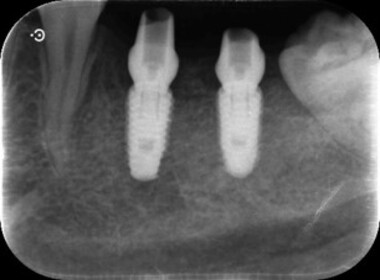

| 0313 #36#37 左下第一第二大臼齒 |

![]() |